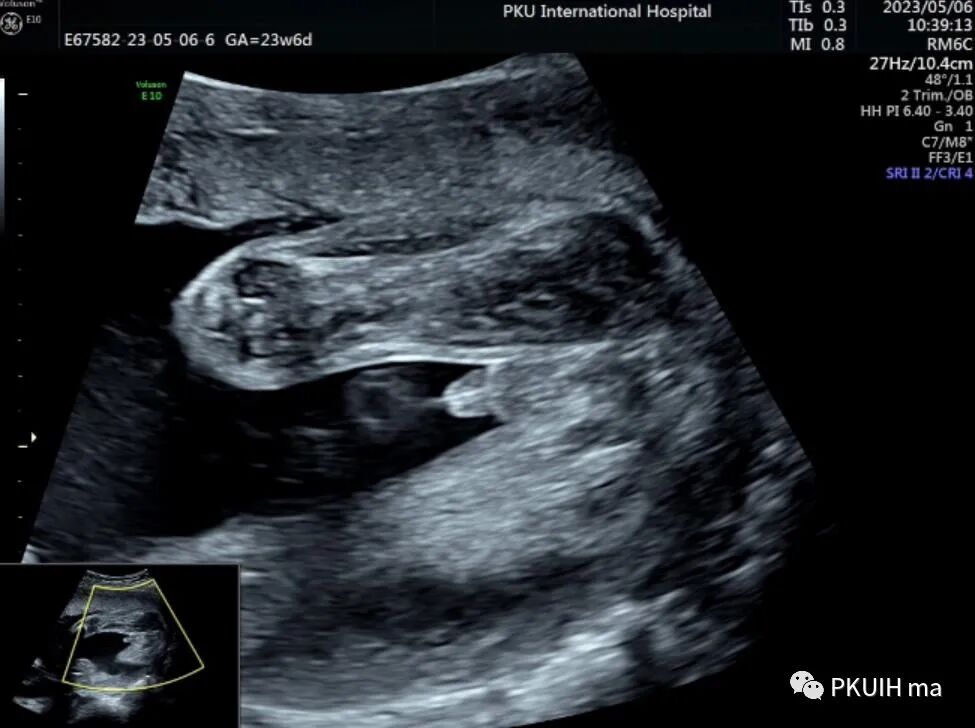

马蹄肾在日常成人超声中并非罕见,发病率约2.5‰,是一种先天肾融合畸形。一般男性多见,男女比例约2:1。通常多是肾下极融合,上极很少见,由于形似马蹄,故名“马蹄肾”。本例马蹄肾胎儿就是一个Boy宝宝,可以观察到胎儿外生殖器呈XY特征,检查中并可见小宝宝正在排尿(见下图)。